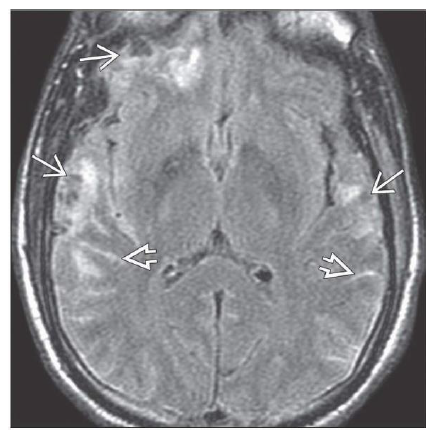

WHAT IS SHOWN?

Axial FLAIR shows multifocal cortical contusions with traumatic SAH, seen as sulcal

hyperintensities adjacent to the lesions